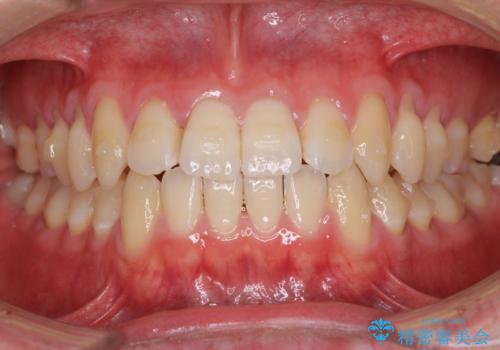

- 上下前歯のデコボコを気にして来院された患者様です。

叢生は軽微であり、費用を抑えて期間もあまりかけずに治療をしたいとのことで、インビザライン・ライトを用いて矯正治療を行うこととしました。

途中通院できなくなり、マウスピースの装着もしっかりとできなかったため、治療期間が長くかかってしまいました。